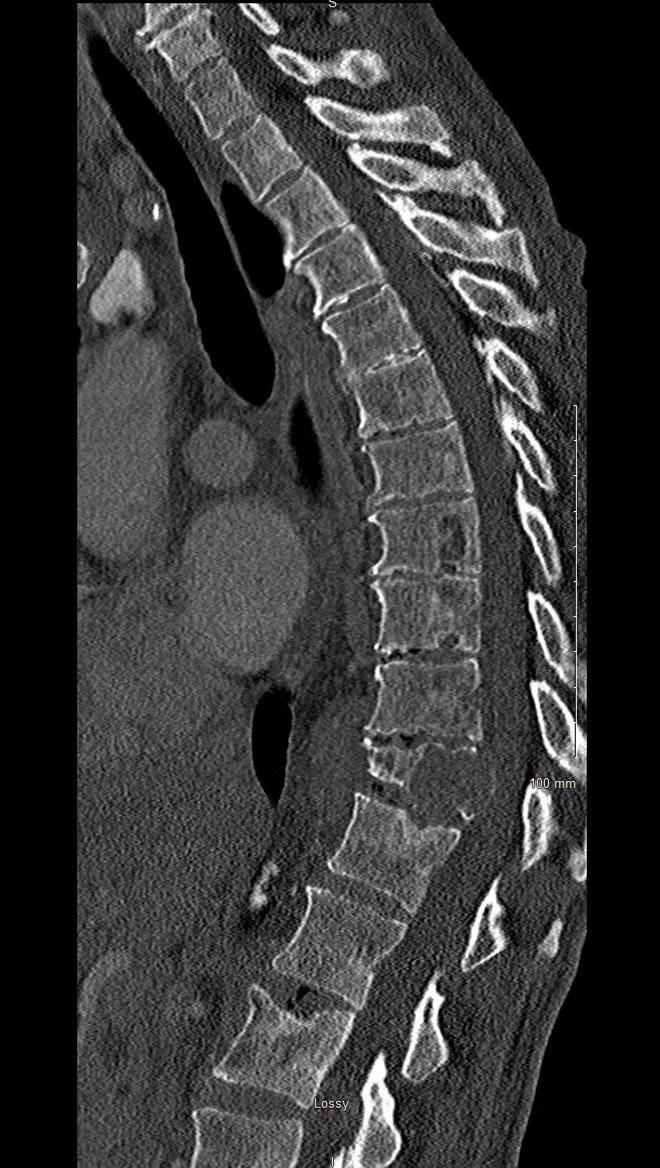

Imaging

Hillengass 2019 Lancet Oncol, Rome 2017 Clin J Oncol, Faiman 2014 Clin Lymphoma Myeloma Leuk, Dimopoulous 2009 Leukemia

Edelstyn 1967 Clin Radiol, Hillengass 2017 BCJ